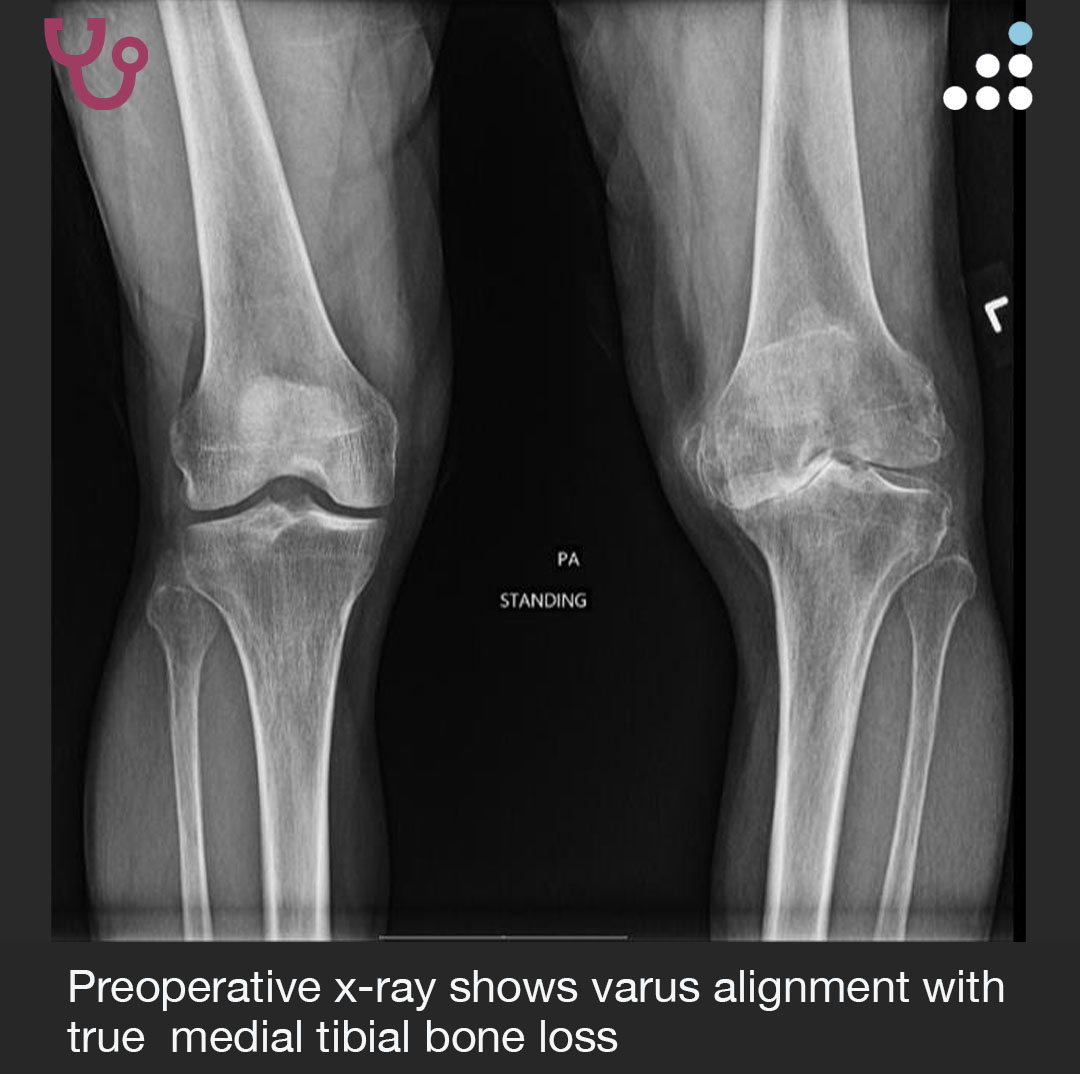

VARUS KNEE IN 61M

How would you manage this #orthotwitter?

Vote on this case for CME: orthobullets.tiny.us/m7wjdzp